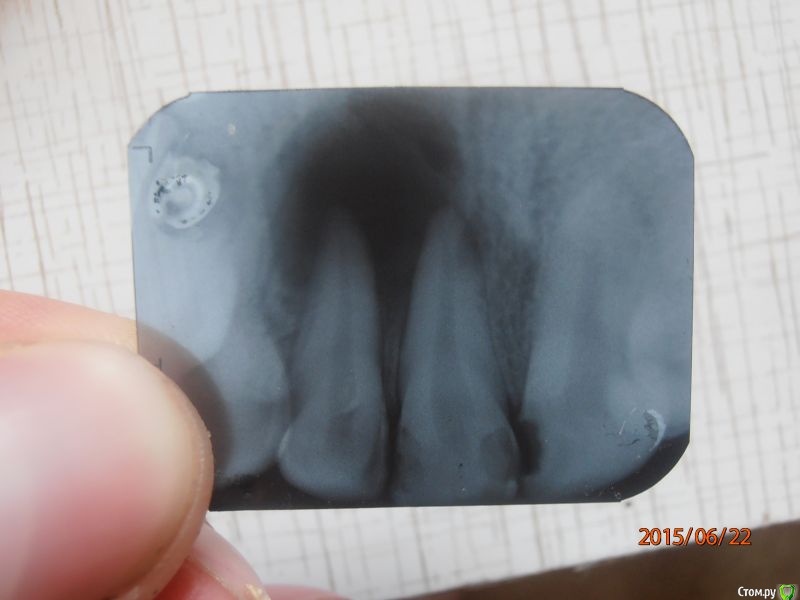

иван37 Опубликовано 22 июня, 2015 Поделиться Опубликовано 22 июня, 2015 (изменено) Подскажите, пожалуйста есть ли смысл лечить данный зуб или удалить и не тратить деньги, на десне свищ, зуб не болит Изменено 22 июня, 2015 пользователем иван37 Ссылка на комментарий

Гарриевич Опубликовано 23 июня, 2015 Поделиться Опубликовано 23 июня, 2015 Обязательно лечите, зуб спасаемы 98% Ссылка на комментарий

иван37 Опубликовано 23 июня, 2015 Автор Поделиться Опубликовано 23 июня, 2015 Спасибо огромное за отклик. Мне хирург сказала положат лекарство на три месяца, а потом резать десну. У нас городок конечно маленький, специалистов мало, но буду пробывать Ссылка на комментарий

red_butler Опубликовано 23 июня, 2015 Поделиться Опубликовано 23 июня, 2015 Хирург не нужен, ищите грамотного терапевта 3 Ссылка на комментарий